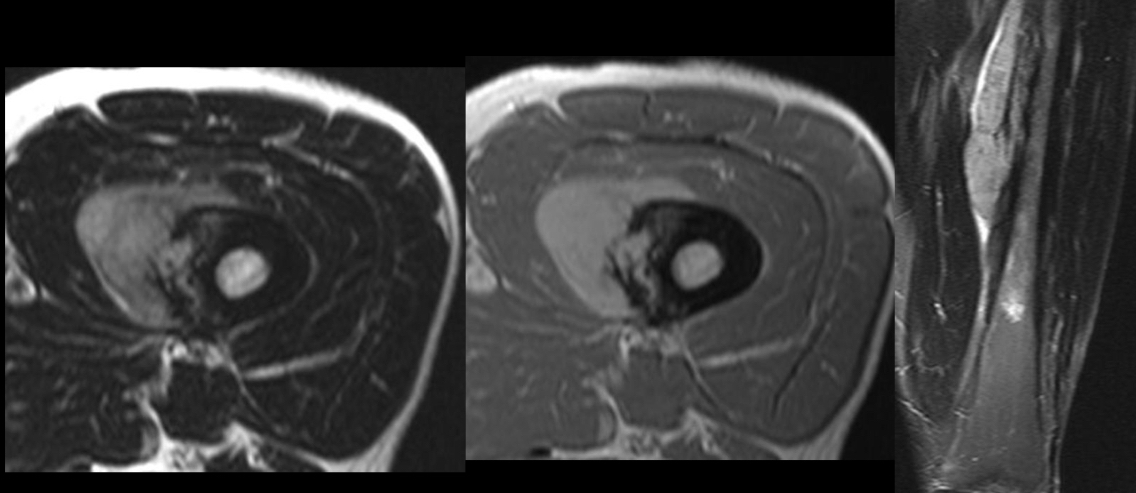

Q

Q se ve y para q sirve rm

A

estadificacion

Determinar conservacion de extremidad

Extension intraosea y a tejido blando

Contraste